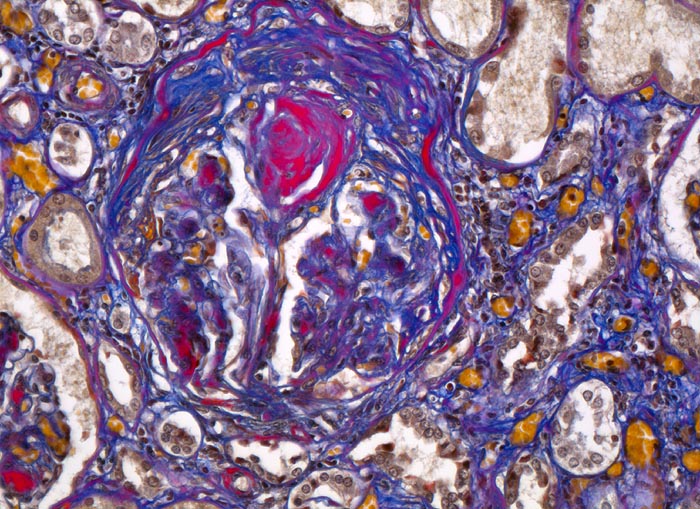

PathoPic – image database / PathoPic ID 4636 - Diabetische noduläre Glomerulosklerose Kimmelstiel-Wilson

Diabetische noduläre Glomerulosklerose Kimmelstiel-Wilson

Niere

Partiell verödetes Glomerulum mit zwiebelschalenartig geschichtetem mesangialem Knoten. Interstitielle Fibrose.

Diabetes mellitus Typ II seit 20 Jahren.

Histologie

200